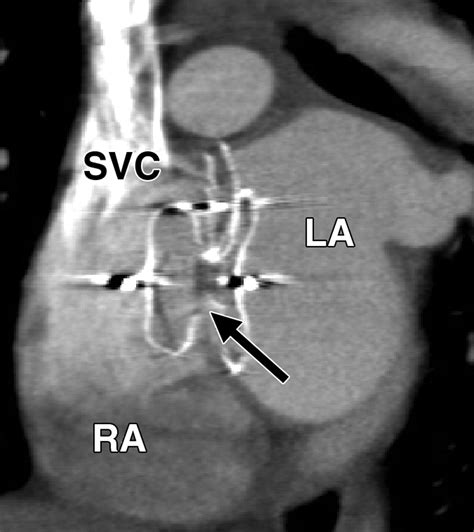

The Amplatzer Septal Occluder is specifically designed to address this by sealing the defect. It is essentially a self-expanding, double-disk device made from a flexible nitinol wire mesh. Once placed, it creates a "sandwich" effect that covers both sides of the hole, allowing the patient's own tissue to grow over the device over time, effectively healing the septal wall.

• Deployment: The Amplatzer Septal Occluder is pushed through the catheter. The left atrial disk is deployed first to anchor the device, followed by the right atrial disk.

• Evaluation: Once the device is in place, the physician ensures it is securely positioned and that the defect is completely closed.